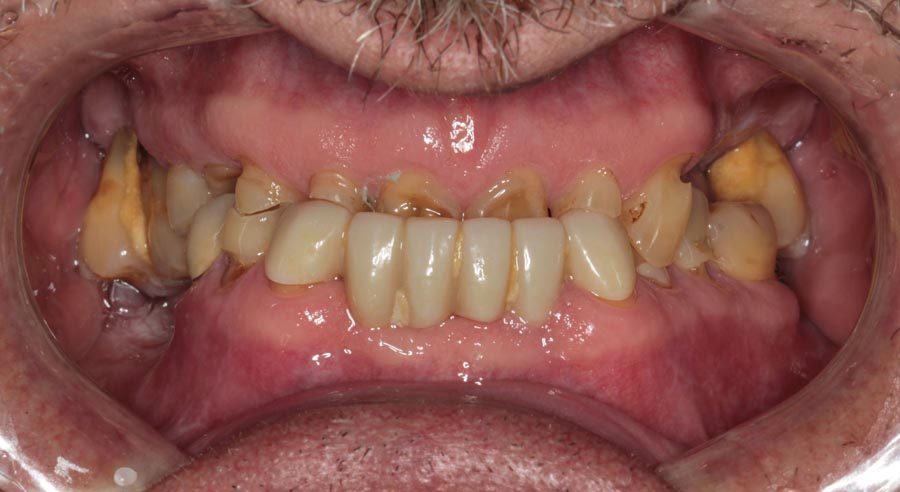

Smile GalleryImplant RestorationsFull Mouth Implant Restoration 1 of 13 Pre-operative smile Pre-operative smile Pre-operative frontal view, lips retracted Pre-operative panoramic image (note bone levels) Post-surgical panoramic image Surgical temporary bridge (note convex contours) Delivery of surgical temporary bridges in both upper and lower Two weeks post-op surgery and temporaries (note amazing tissue response) Three months post- surgery. (Note tissue development) Definitive implant bridges (FP-2) Post-treatment panoramic image Final result smile Final result smile